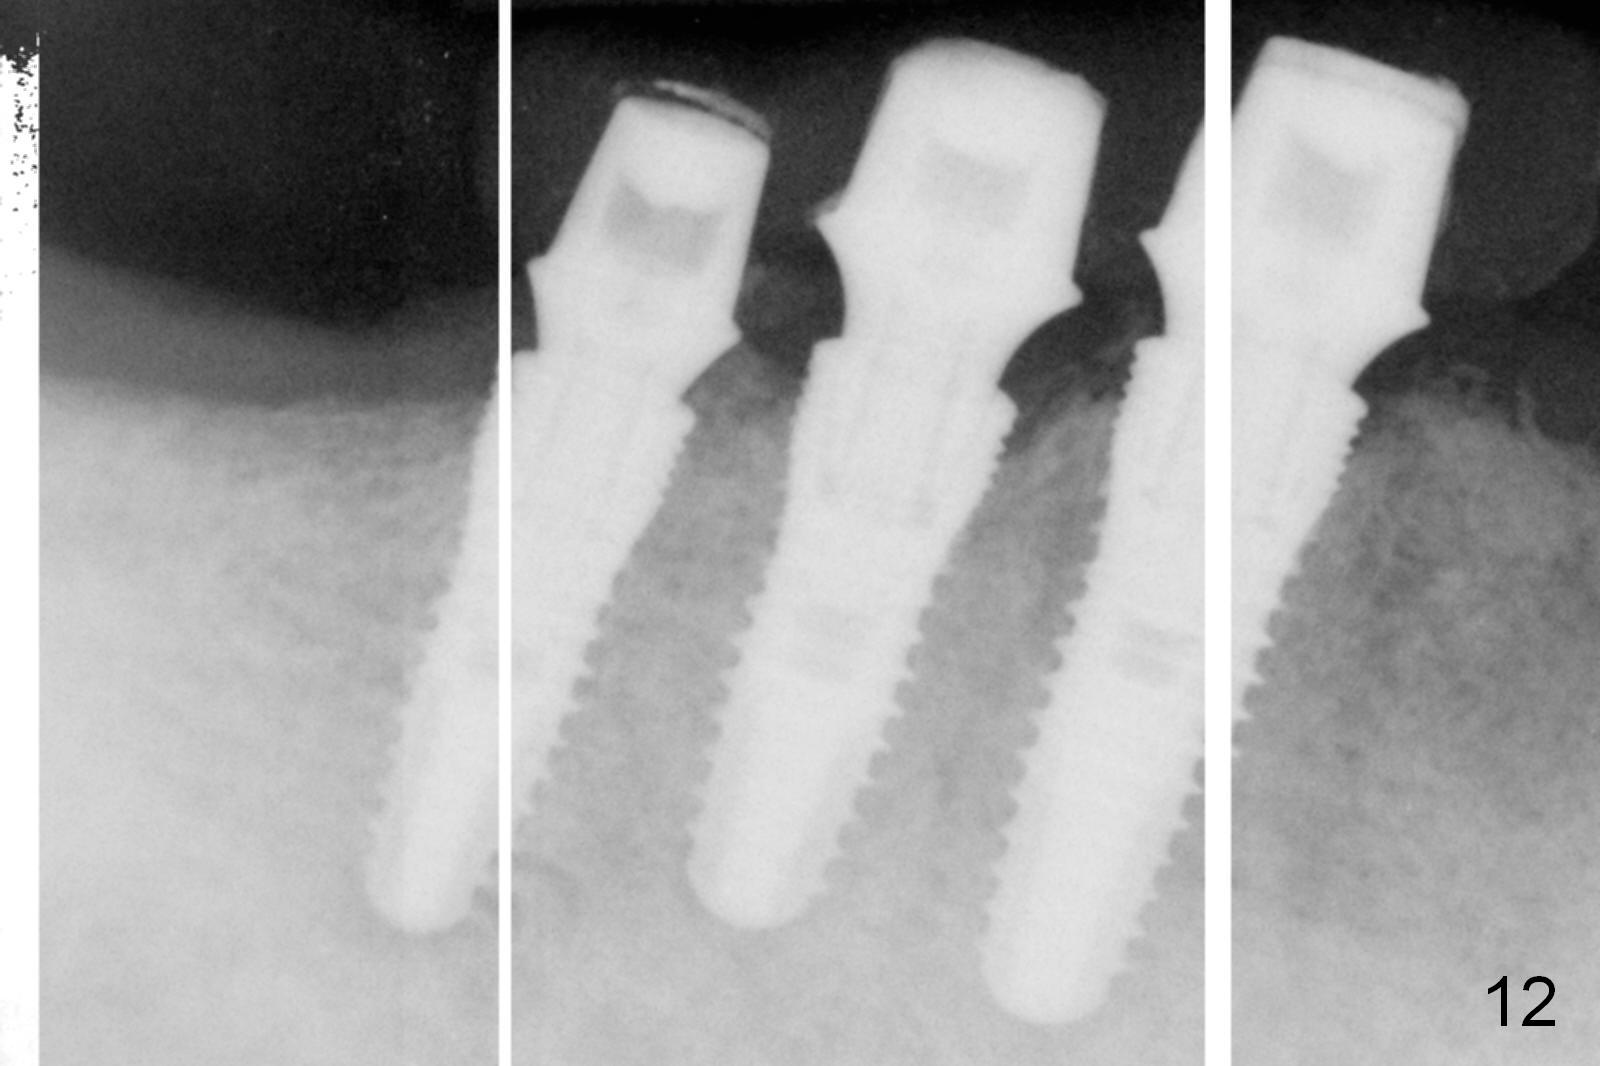

The patient returns for definitive restoration 5 months postop. There is no gross bone resorption around the implants (Fig.12). The surrounding gingiva is healthy (Fig.13). Since the edentulous space at #26 is relatively wide, one option is to splint #26-28 with #29 single. If the abutments at #27 and 28 are not parallel and the gingival margins are not at the same level too much, simply splint #26 and 27, since the implant at #27 is relatively long and wide.

In fact, the crowns are splinted between #26-28, while the one at #29 is single unit (Fig.14). The patient is concerned that the bite on the lower right side is not strong. The occlusion for the most distal crowns should be tight.